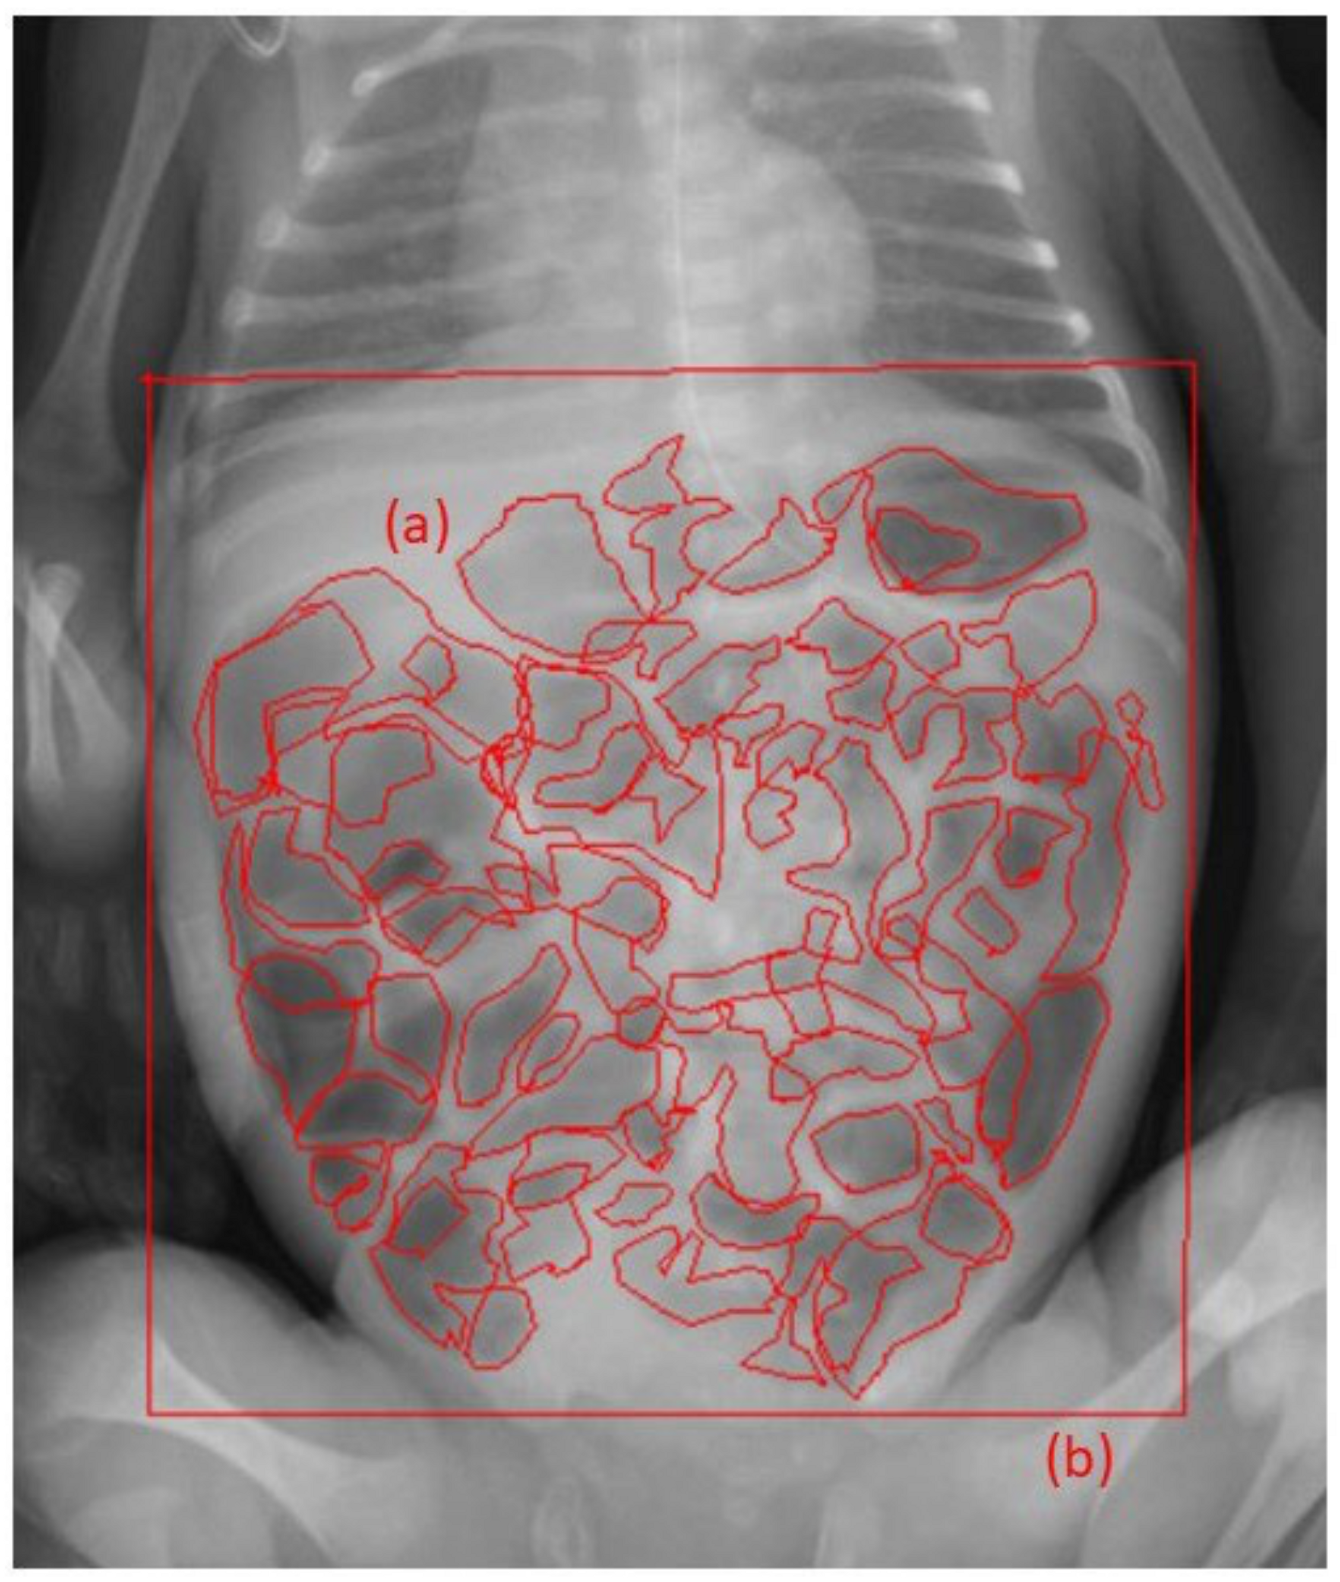

2.5. Evaluation of Abdominal Gas Areas

- Koide, A.; Yamaguchi, T.; Odaka, T.; Koyama, H.; Tsuyuguchi, T.; Kitahara, H.; Ohto, M.; Saisho, H. Quantitative analysis of bowel gas using plain abdominal radiograph in patients with irritable bowel syndrome. Am. J. Gastroenterol. 2000, 95, 1735–1741. [Google Scholar] [CrossRef]